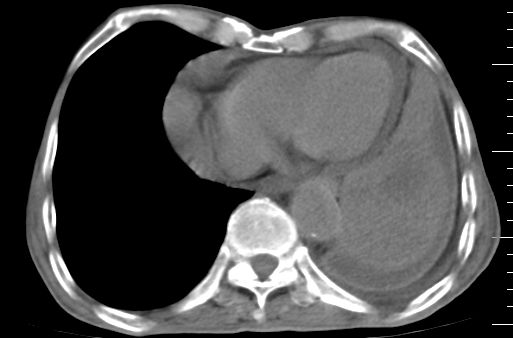

标题: CT10141:男、84岁,咳嗽、咯血1年。 [打印本页]

标题: CT10141:男、84岁,咳嗽、咯血1年。

支持左侧中央型肺癌伴下叶肺不张\\纵隔淋巴结转移.左侧包裹性胸腔积液\\心包积液.左侧少量胸腔积液..慢性支气管炎伴部分间质纤维化.

左肺中心性肺癌并肺不张,同侧 胸膜及心包转移,左肺癌性淋巴管炎

左肺中心性肺癌并左肺下叶肺不张,纵隔淋巴转移、同侧胸腔及心包积液(转移)。